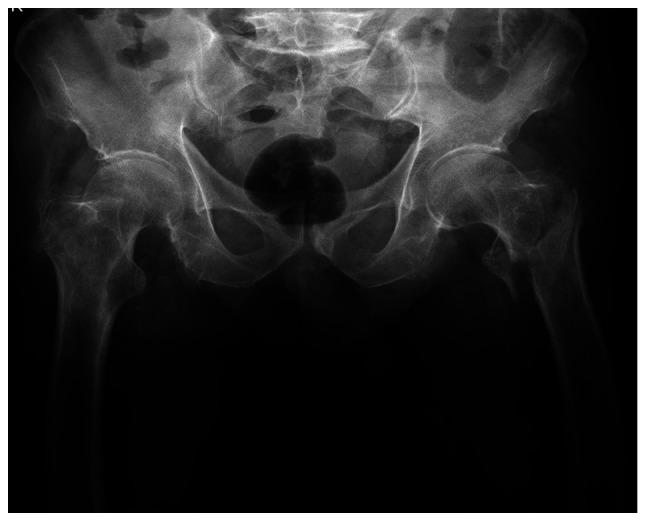

Uncommon causes of nail failures and surgical reinterventions were determined. The study included 23 osteoporotic patients, 13 of whom followed a fast recovery program with early walking (FWB group). The other 10 patients were not allowed full weight bearing until 6 weeks (NFWB group). The T-score was determined before surgery for all cases. A case with a nail breakage after a failed DCS implant fixed in another clinic was also analyzed. The nail was revised and the broken implant underwent a metallurgic and microscopic examination. The average T-score was 2.5 for the patients that followed the fast recovery program and 2.7 for the patients from non-full weight bearing. Four patients, 1 from the NFWB group and 3 from FWB group, presented a screw cut-out. It was found that the errors of the guiding instruments may create dents, scratches or micro-fractures on the titanium coating that lead to an early implant failure. Imperfect reduction leads to incorrect implant placement and a high incidence of failure. Damaging the titanium protective coating, in a low force, high cycles scenario can cause structural failure. Delays in fracture healing and material fatigue are the most common causes of nail failure and can lead to catastrophic complications.

确定了钉失败和手术再次干预的罕见原因。该研究纳入了23名骨质疏松患者,其中13名遵循快速康复计划并早期负重行走(早期负重行走组)。另外10名患者直到6周后才允许完全负重(非完全负重组)。对所有病例在手术前测定T值。还分析了1例在另一家诊所植入失败的DCS钉断裂的病例。对钉进行了翻修,并对断裂的植入物进行了金相和显微镜检查。遵循快速康复计划的患者平均T值为2.5,非完全负重患者的平均T值为2.7。4名患者出现螺钉穿出,其中1名来自非完全负重组,3名来自早期负重行走组。发现导向器械的误差可能在钛涂层上造成凹痕、划痕或微骨折,从而导致植入物早期失败。复位不完善会导致植入物放置不正确和高失败率。在低力、高循环情况下损坏钛保护涂层会导致结构失效。骨折愈合延迟和材料疲劳是钉失败的最常见原因,可导致灾难性并发症。